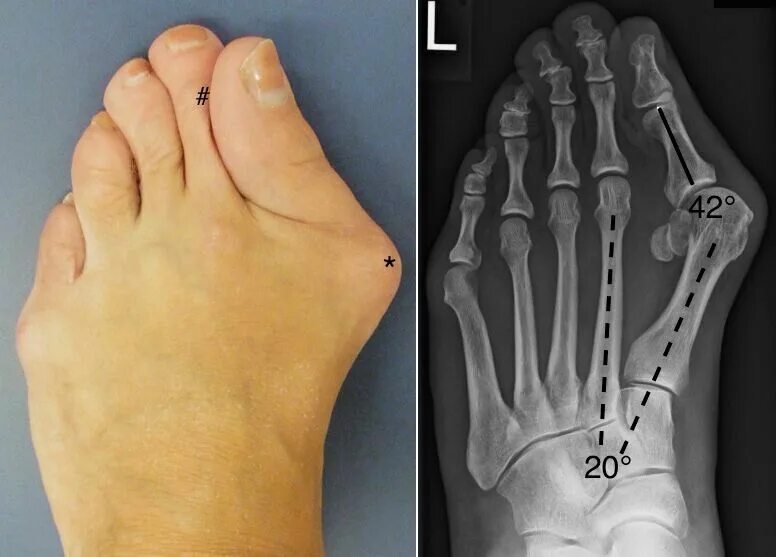

Операция на косточки как называется